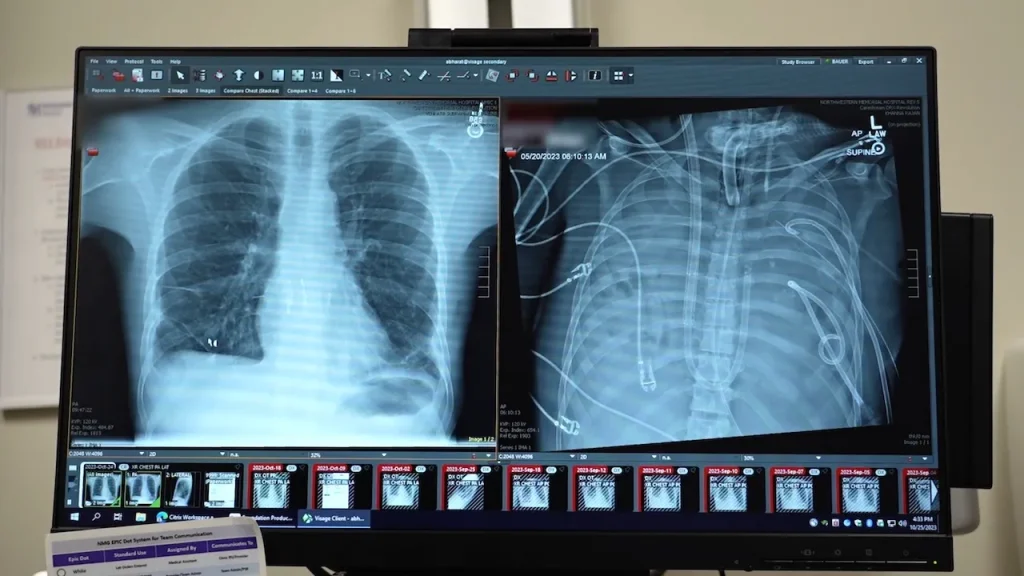

In a groundbreaking medical achievement, surgeons at Northwestern Medicine in Chicago successfully kept a 33-year-old patient alive for 48 hours after removing both of his lungs. The Missouri resident, whose name has not been disclosed, was initially transported to Northwestern Memorial Hospital in spring 2023 with severe lung failure resulting from a flu infection.

The patient’s condition rapidly deteriorated into severe pneumonia and sepsis, causing his heart to stop and requiring CPR, according to the hospital’s press release. Dr. Ankit Bharat, chief of thoracic surgery and executive director of the Northwestern Medicine Canning Thoracic Institute, explained the severity of the situation.

The details of this remarkable case were published last week in the Cell Press journal Med. The study included a molecular analysis of the removed lungs, revealing extensive scarring and tissue damage. This finding supports the notion that in some severe cases of acute respiratory distress syndrome, transplantation may be the only viable treatment option.